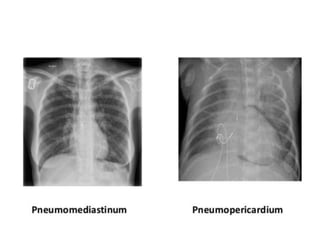

This document provides an overview of interpreting chest x-rays and identifies several key factors. It discusses the importance of inspiration, penetration, and rotation in obtaining a technically quality radiograph. It also outlines different views of chest x-rays including PA, AP, and lateral views. Finally, it identifies several anatomical structures that should be evaluated when interpreting a chest x-ray such as the lungs, heart, diaphragm, bones, and soft tissues.